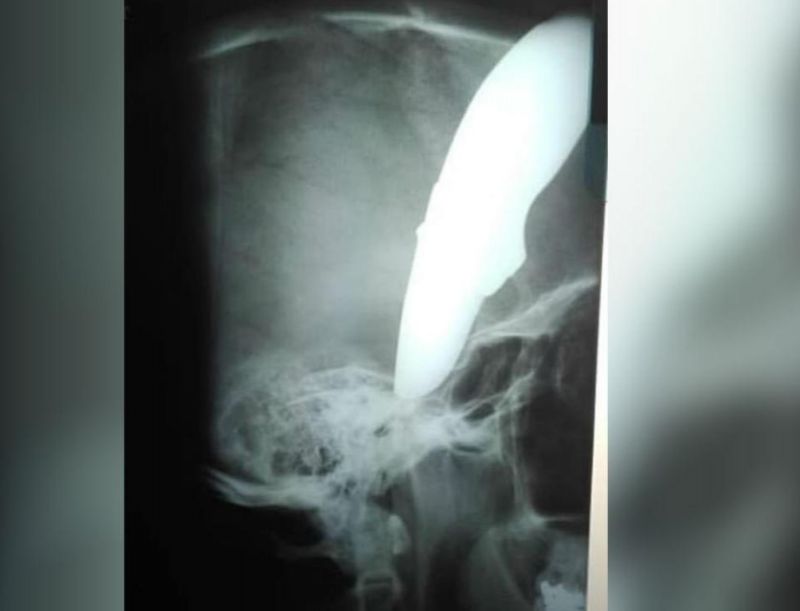

ਕੇਪਟਾਉਨ (ਭਾਸ਼ਾ): ਸਾਉਥ ਅਫਰੀਕਾ ਦੇ ਕੇਪਟਾਉਨ 'ਚ ਇਕ ਸ਼ਖਸ ਸਾਈਕਲ 'ਤੇ ਆਫਿਸ ਜਾ ਰਿਹਾ ਸੀ। ਉਦੋਂ ਉਸਦਾ ਸਾਮਣਾ ਕੁੱਝ ਬਦਮਾਸ਼ਾਂ ਨਾਲ ਹੋਇਆ। ਬਦਮਾਸ਼ਾਂ ਨੇ ਸ਼ਖਸ ਦੇ ਸਿਰ 'ਚ ਚਾਕੂ ਮਾਰ ਦਿਤਾ। 34 ਸਾਲ ਦਾ ਸ਼ਾਨ ਵਾਇਨ ਰੋਜ਼ ਦੀ ਤਰ੍ਹਾਂ ਅਪਣੀ ਸਾਈਕਲ ਤੋਂ ਆਫਿਸ ਜਾ ਰਹੇ ਸੀ। ਉਦੋਂ ਦੋ ਲੁਟੇਰਿਆਂ ਨੇ ਉਸ 'ਤੇ ਹਮਲਾ ਕਰ ਉਸ ਦੀ ਸਾਈਕਲ ਖੋਹਣ ਦੀ ਕੋਸ਼ਿਸ਼ ਕੀਤੀ।

ਲੁਟੇਰਿਆਂ ਅਤੇ ਸ਼ਾਨ ਦੇ 'ਚ ਹਾਥੋਪਾਈ ਹੋਈ ਅਤੇ ਇੱਕ ਲੁਟੇਰੇ ਨੇ ਉਨ੍ਹਾਂ ਦੇ ਸਿਰ 'ਚ ਚਾਕੂ ਮਾਰ ਦਿਤਾ । ਗੰਭੀਰ ਰੂਪ 'ਚ ਜਖ਼ਮੀ ਹੋਣ ਤੋਂ ਬਾਅਦ ਵੀ ਉਹ ਲੁਟੇਰਿਆਂ ਨੂੰ ਭਜਾਉਣੇ 'ਚ ਕਾਮਯਾਬ ਰਿਹਾ। ਸ਼ਾਨ ਨੇ ਹਿੰਮਤ ਨਾਂ ਹਾਰਦੇ ਹੋਏ ਉਸ ਨੇ ਖੁਦ ਸਾਈਕਲ ਚੁੱਕ ਕੇ ਅਤੇ ਸਿਰ 'ਚ ਧਸੇ ਚਾਕੂ ਦੇ ਨਾਲ ਖੁਦ 1 ਕਿਲੋਮੀਟਰ ਤੱਕ ਸਾਈਕਲ ਚਲਾ ਕੇ ਹਸਪਤਾਲ ਪਹੁੰਚ ਗਿਆ।

ਜਿਸ ਨੇ ਸਾਰਿਆਂ ਨੂੰ ਹੈਰਾਨ ਕਰ ਦਿਤਾ। ਹਸਪਤਾਲ ਦਾ ਸਟਾਫ ਉਸ ਨੂੰ ਵੇਖਕੇ ਹੈਰਾਨ ਰਹਿ ਗਿਆ ਅਤੇ ਤੁਰੰਤ ਉਸ ਦਾ ਇਲਾਜ ਸ਼ੁਰੂ ਕਰ ਦਿਤਾ। ਰਿਪੋਰਟਸ ਦੇ ਮੁਤਾਬਕ ਸ਼ਾਨ ਦੀ ਹਾਲਾਤ ਹੁਣੇ ਬਿਹਤਰ ਹੈ। ਪੁਲਿਸ ਵਲੋਂ ਮਾਮਲੇ ਦੀ ਛਾਨਬੀਨ ਚੱਲ ਕੀਤੀ ਜਾ ਰਹੀ ਹੈ। ਦੱਸ ਦਈਏ ਕਿ ਉਸ ਦੀ ਬਹਾਦਰੀ ਦੀਆਂ ਸਿਫਤਾਂ ਕਰ ਰਿਹਾ ਹੈ ਕਿ ਉਸ ਨੇ ਅਜਿਹੇ ਸਮੇਂ 'ਚ ਹਿੰਮਤ ਨਹੀਂ ਛੱਡੀ।